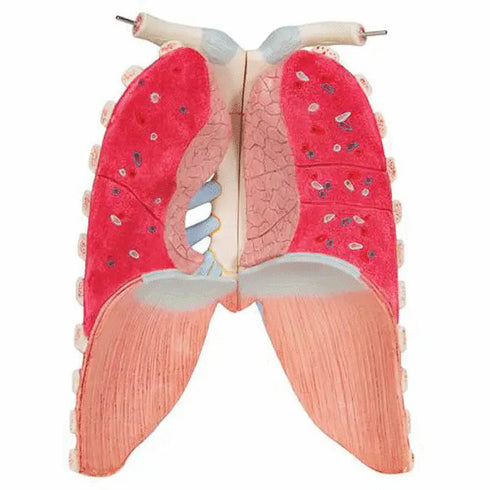

- plamani cu stern si coaste (2 parti);